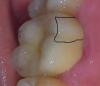

ermol Опубликовано 17 октября, 2012 Поделиться Опубликовано 17 октября, 2012 (изменено) Здравствуйте. Подскажите пожалуйста. Лет 8 назад удалили корни на шестом зубе сверху. Стояла большая пломба.4 дня назад у меня вертикально откололся кусок стенки зуба, примерно 1/4 зуба и в глубину наверное на 1мм ниже десны. Примерно так —(зуб на фото не мой) Вот снимок моего зуба - В первой клинике то что отломилось удалили, поставили временную пломбу. И собственно предлагали делать так:-Перепломбировка каналов-Установка вкладки под коронку-Металлокерамическая коронкаПо поводу штифта сказали если вворачивать штифт, то может треснуть оставшиеся стенки (но не уверен что говорили именно про стенки). В общем, были против. В другой стоматологии сказали так - Что перепломбирвать ничего не надо, достаточно вкрутить штифты и поставим МК коронку. На вопрос по поводу вкладки сказал что по своему опыту ставит штифты и никаких проблем с этим нет. По цене этот вариант в 2,5 раза ниже чем в первой клинике. Дайте совет что лучше делать на Ваш взгляд. Изменено 17 октября, 2012 пользователем ermol 1 Ссылка на комментарий

ermol Опубликовано 19 октября, 2012 Автор Поделиться Опубликовано 19 октября, 2012 А каналы обязательно перелечивать под вкладку? Вот снимок получше. Ссылка на комментарий